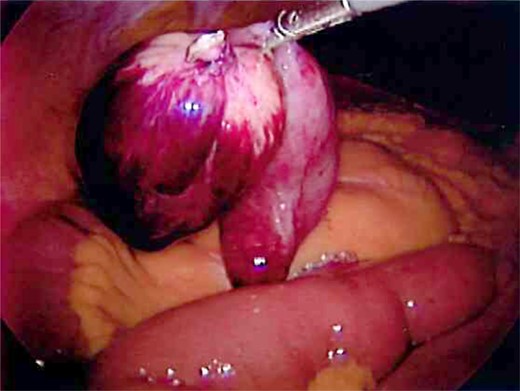

Laparoscopy was performed and a large Meckel's diverticulum was identified ∼30 cm proximal from the ileocecal valve. It had twisted 360° and was swollen and gangrenous at the distal half (Fig. 1). The tip of the diverticulum contained a 3-cm long mesodiverticular band that was attached to the mesentery of an adjacent loop of terminal ileum (Fig. 2). The mesodiverticular band was surgically divided, and the diverticulum was then de-torsed revealing a normal appearing base (Fig. 3). The diverticulum was excised along its base using an endoscopic stapler (Fig. 4). The surgery was completed with an appendectomy. On postoperative day one, the patient was doing well and was discharged home.

Excised Meckel's diverticulum before removal from the abdomen.